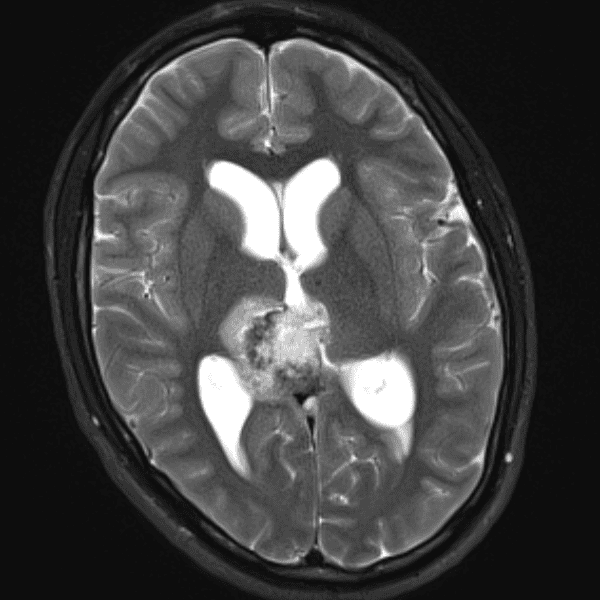

Classic Cases